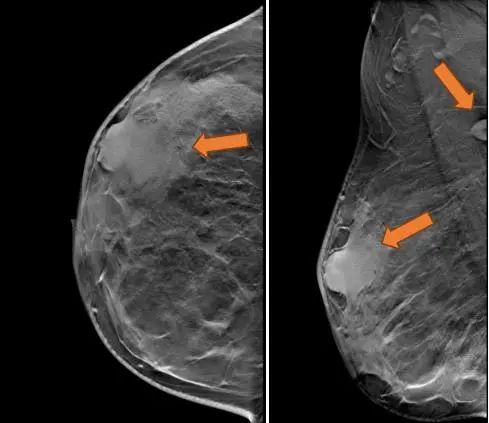

2021.7.6 钼靶示:右乳外上象限肿块,考虑乳腺癌(BI-RADS-5类)右腋下肿大淋巴结,M灶可能。

右乳外上象限不规则高密度肿块,边缘毛糙,大小约3.3×2.7cm,邻近皮肤牵拉增厚,右腋下见肿大淋巴结。

图2. 钼靶

(3 cycle 后)2021.9.21 钼靶示:右乳外上象限不规则形肿块明显缩小,右腋窝淋巴结亦较前缩小。

图6. 钼靶